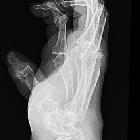

Hands and wrists

Diagnosis and follow-up of patients with RA commonly involve imaging of the hands and wrists. The disease tends to affect the proximal joints in a bilaterally symmetrical distribution.

RA is a synovial based process, with a predilection for:

- PIP and MCP joints (especially 2 and 3 MCP)

- ulnar styloid

- triquetrum

As a rule, the DIP joints are spared.

Late changes include:

- subchondral cyst formation: the destruction of cartilage presses synovial fluid into the bone

- subluxation causing:

- ulnar deviation of the MCP joints

- boutonniere and swan neck deformities

- hitchhiker’s thumb deformity

- carpal instability: scapholunate dissociation, ulnar translocation

- ankylosis

- scallop sign: erosion of the ulnar aspect of the distal radius which may be predictive of extensor tendon rupture (Vaughan-Jackson syndrome)